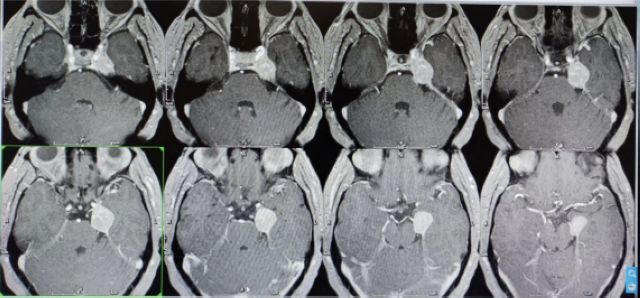

伽玛刀治疗前

伽玛刀治疗后